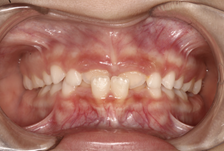

En el examen intraoral se observa mordida cruzada anterior. Las líneas medias dentales coinciden. Esto indica correcta alineación central. Tanto el arco superior como el inferior presentan forma en U, lo que sugiere un buen espacio para la dentición y una correcta disposición de los dientes en ambos arcos.

Figura 4. Mordida cruzada anterior Figura 5. Arco superior en forma de U

Figura 6. Arco interior en forma de U